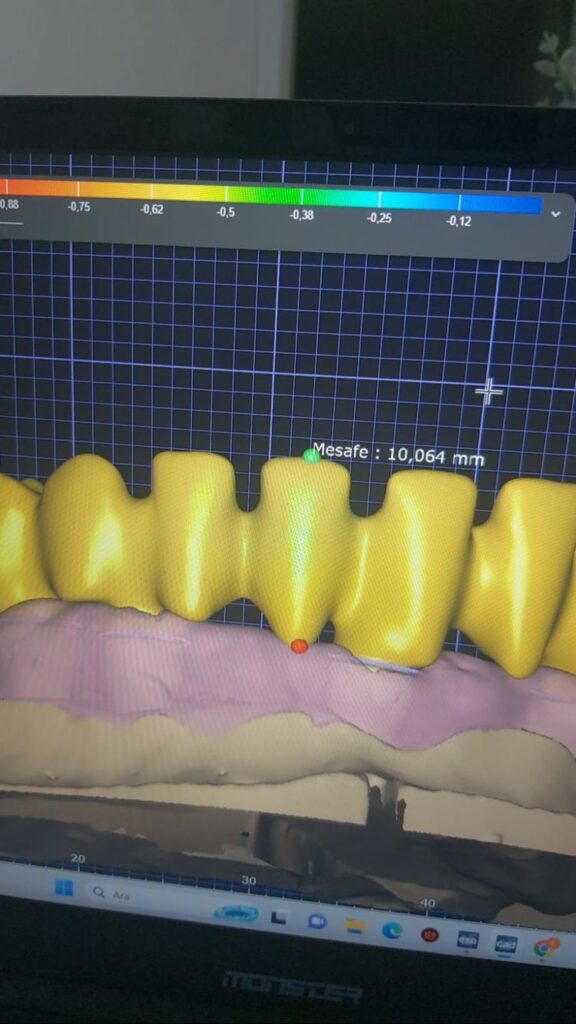

IMPLANT USTU ZIRKONYUM

IMPLANT USTU ZIRKONYUM ALT YAPI

MONOLITIK IMPLANT USTU ZIRKONYUM & ÜSTTEN ViDALI ZİRKONiUM

MULTILAYER IMPLANT ÜSTÜ ZIRKONYUM & ÜSTTEN VİDALI ZIRKONYUM